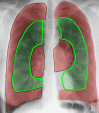

Endobronchial coils are an additional treatment option for lung volume reduction in patients with severe emphysema. Patient selection should be focused on patients with severe emphysema on optimal medical therapy and with evidence of severe hyperinflation. The technique is suitable in a broad range of patients with emphysema; however, patients with paraseptal emphysema, large focal (giant) bullae, significant co-morbidity and airway-predominant disease should be avoided. Treatment involves placing between 10 and 14 coils by bronchoscopy in the selected treatment lobe, with 2 lobes being treated sequentially. Lobe selection for treatment should be based on quantitative computed tomography, and the lobes with the greatest destruction should be targeted (excluding the right middle lobe). The treatment results in an improvement in pulmonary function, exercise performance and quality of life, particularly in patients with severe hyperinflation (residual volume > 200% predicted) and upper-lobe heterogeneous emphysema, but will also be of benefit in lower-lobe predominant and homogeneous emphysema. Finally, it has an acceptable safety profile, although special attention has to be paid to coil-associated opacity which is an inflammatory response that occurs in some patients treated with endobronchial coils.